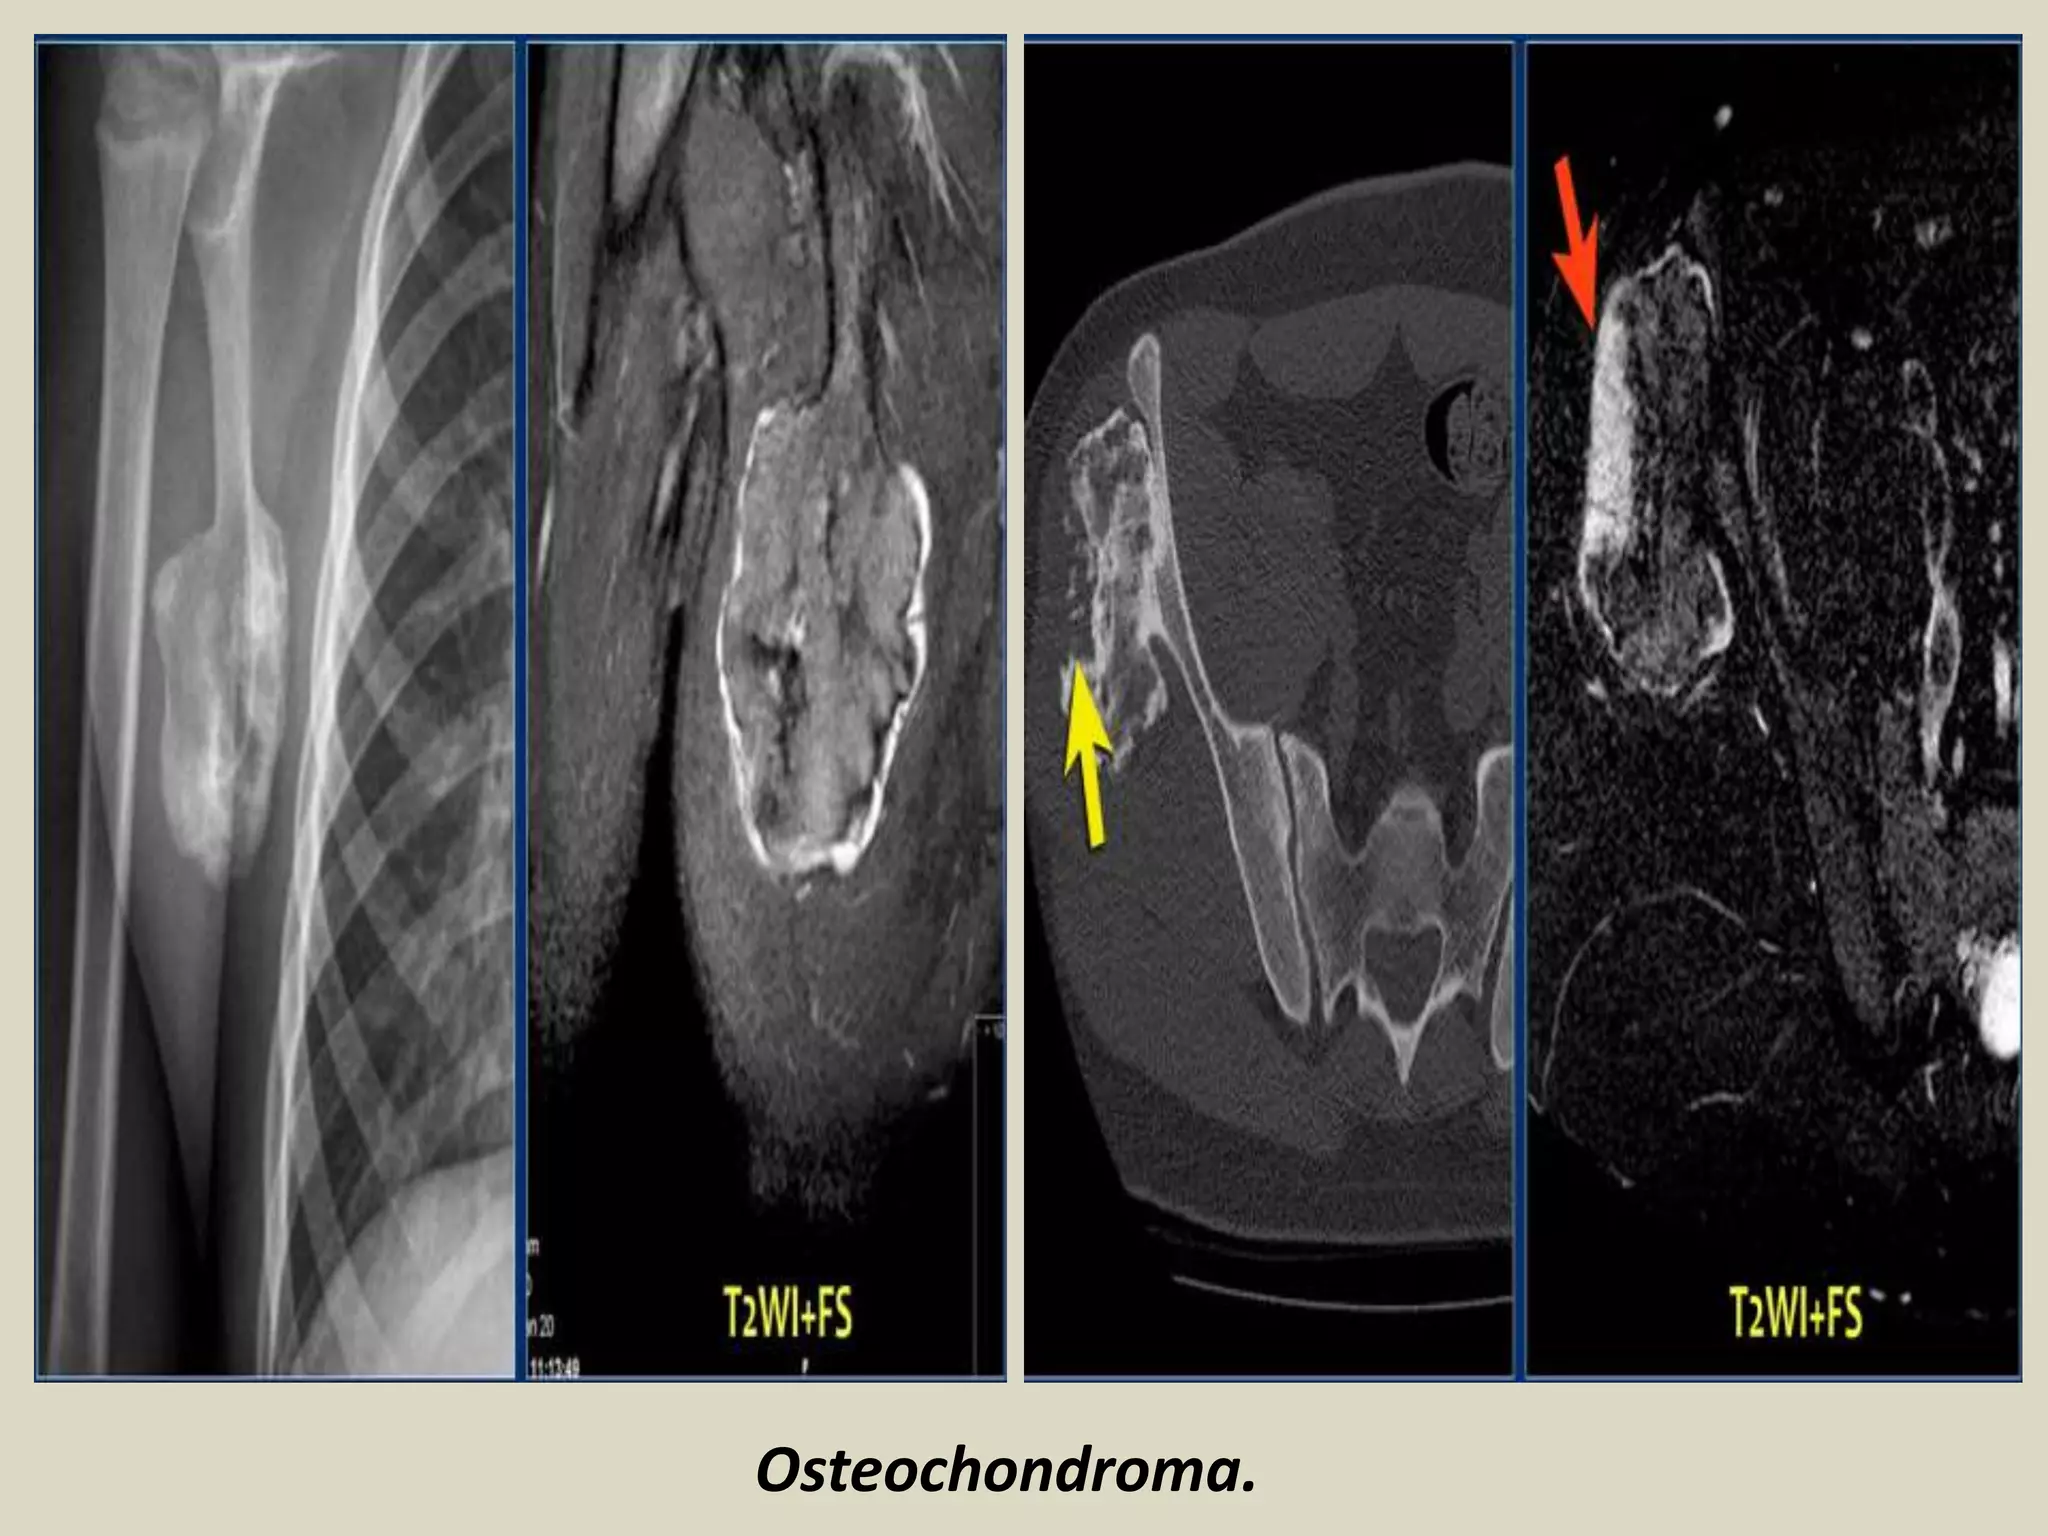

OSTEOCHONDROMA (EXOSTOSIS)

Definition: Cartilage capped bony projection arising on the external surface of bone containing

a marrow cavity that is continuous with that of the underlying bone.

Imaging:

- Bulbous lesions on X rays, and they a narrow or broad (sessile) osseous radiosense stalk, which is attached

to the underlying bone.

- The characteristic feature is a projection of the cortex in continuity with the underlying bone.

- Excessive cartilage type flocculent calcification should raise the suspicion of malignant transformation.

- CT scan or MRI images typically show continuity of the marrow space into the lesion. A thick cartilaginous

cap rises suspicion of malignant transformation.

Osteochondroma.